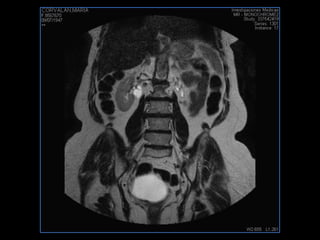

LIC ALEJANDRA GALVEZ RM DE ABDOMEN

resonancia de abdomen